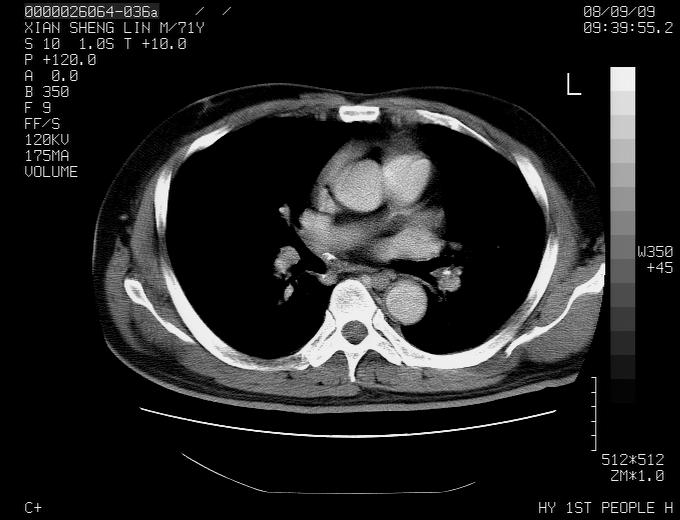

标题: CT15869:男性,71岁,因咳嗽而就诊,请讨论右上肺病变性质 [打印本页]

标题: CT15869:男性,71岁,因咳嗽而就诊,请讨论右上肺病变性质

患者,男性,71岁,因咳嗽而就诊,

典型的右肺中心性肺癌并纵隔淋巴结转移

右肺中心性肺癌并纵隔淋巴结转移可能性大!

病灶中等程度强化 还是支持肺癌诊断

考虑右肺中心性肺癌并右肺门及纵隔淋巴结转移。

1,右肺中心型ca,气管隆突旁淋巴结转移。

2,右膈明显抬高,建议肝脏扫描排除转移或原发灶。